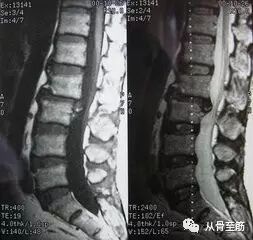

? ? MRI大多情况下优于CT,特别是在椎间盘突出、感染和肿瘤的诊断上,能清楚地显示椎间盘的类型(尤其是脱垂游离型,可清楚显示椎间盘向后下游离,对部分向上游离的椎间盘可明显减少漏诊)和硬脊膜和神经根受压程度。但在显示骨皮质、钙化或骨化组织又不如CT。